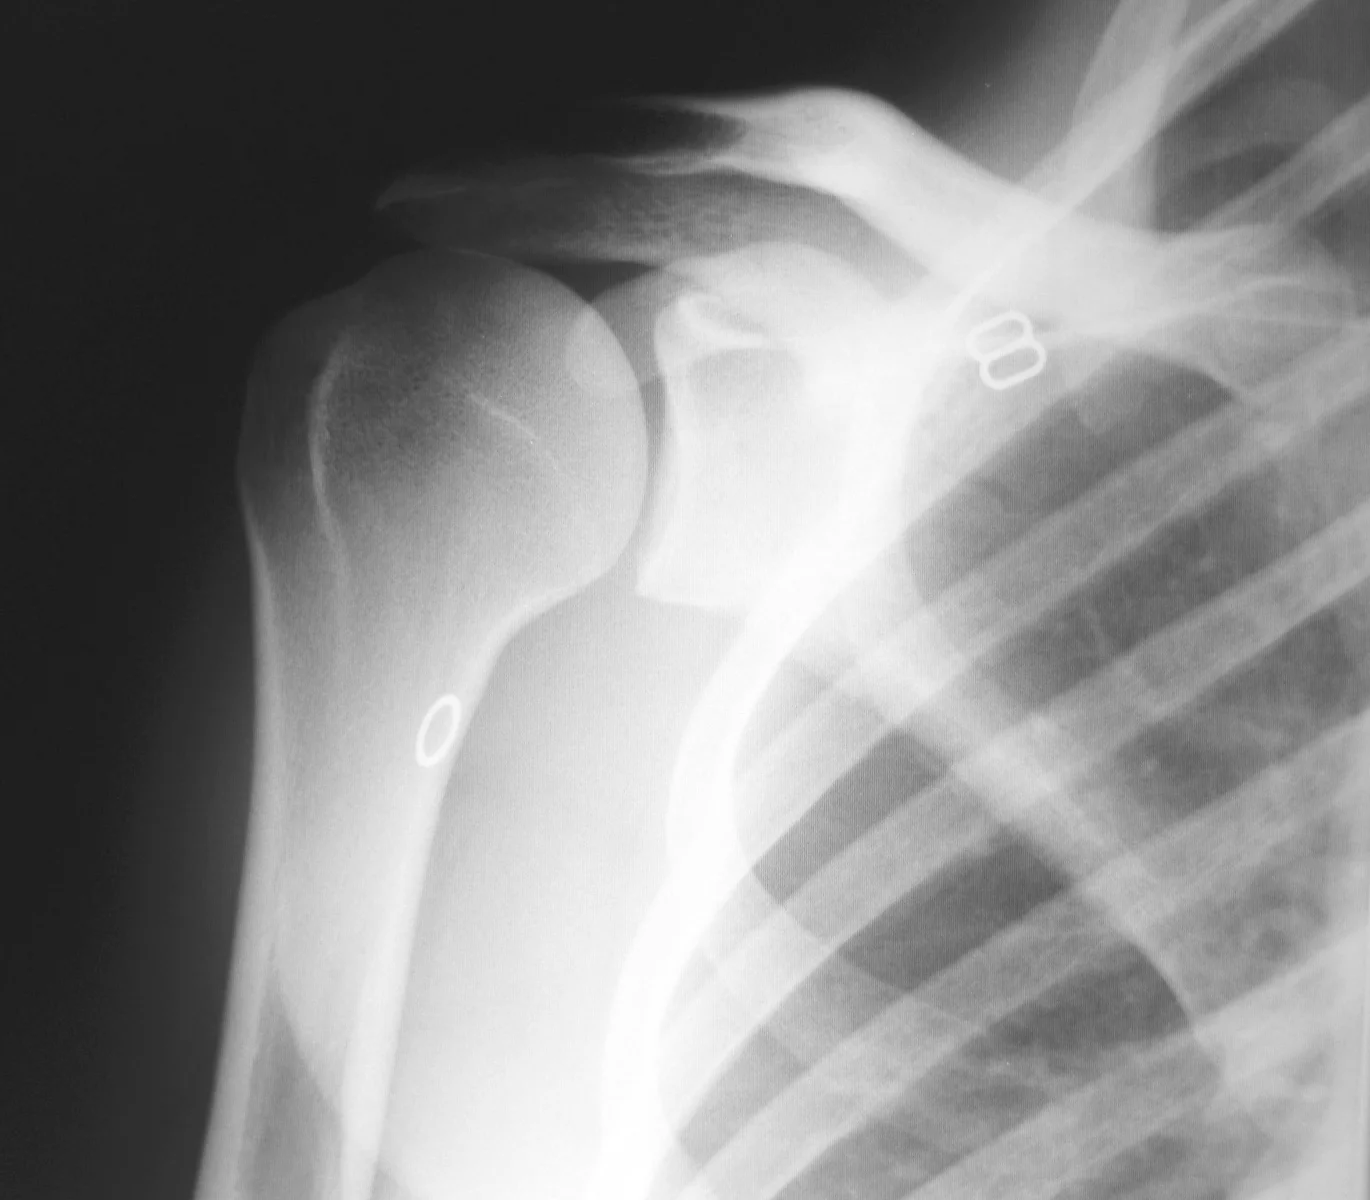

X-ray of arthritic shoulder